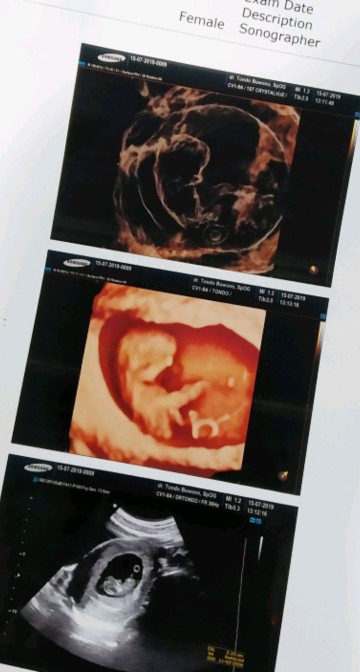

10w5d